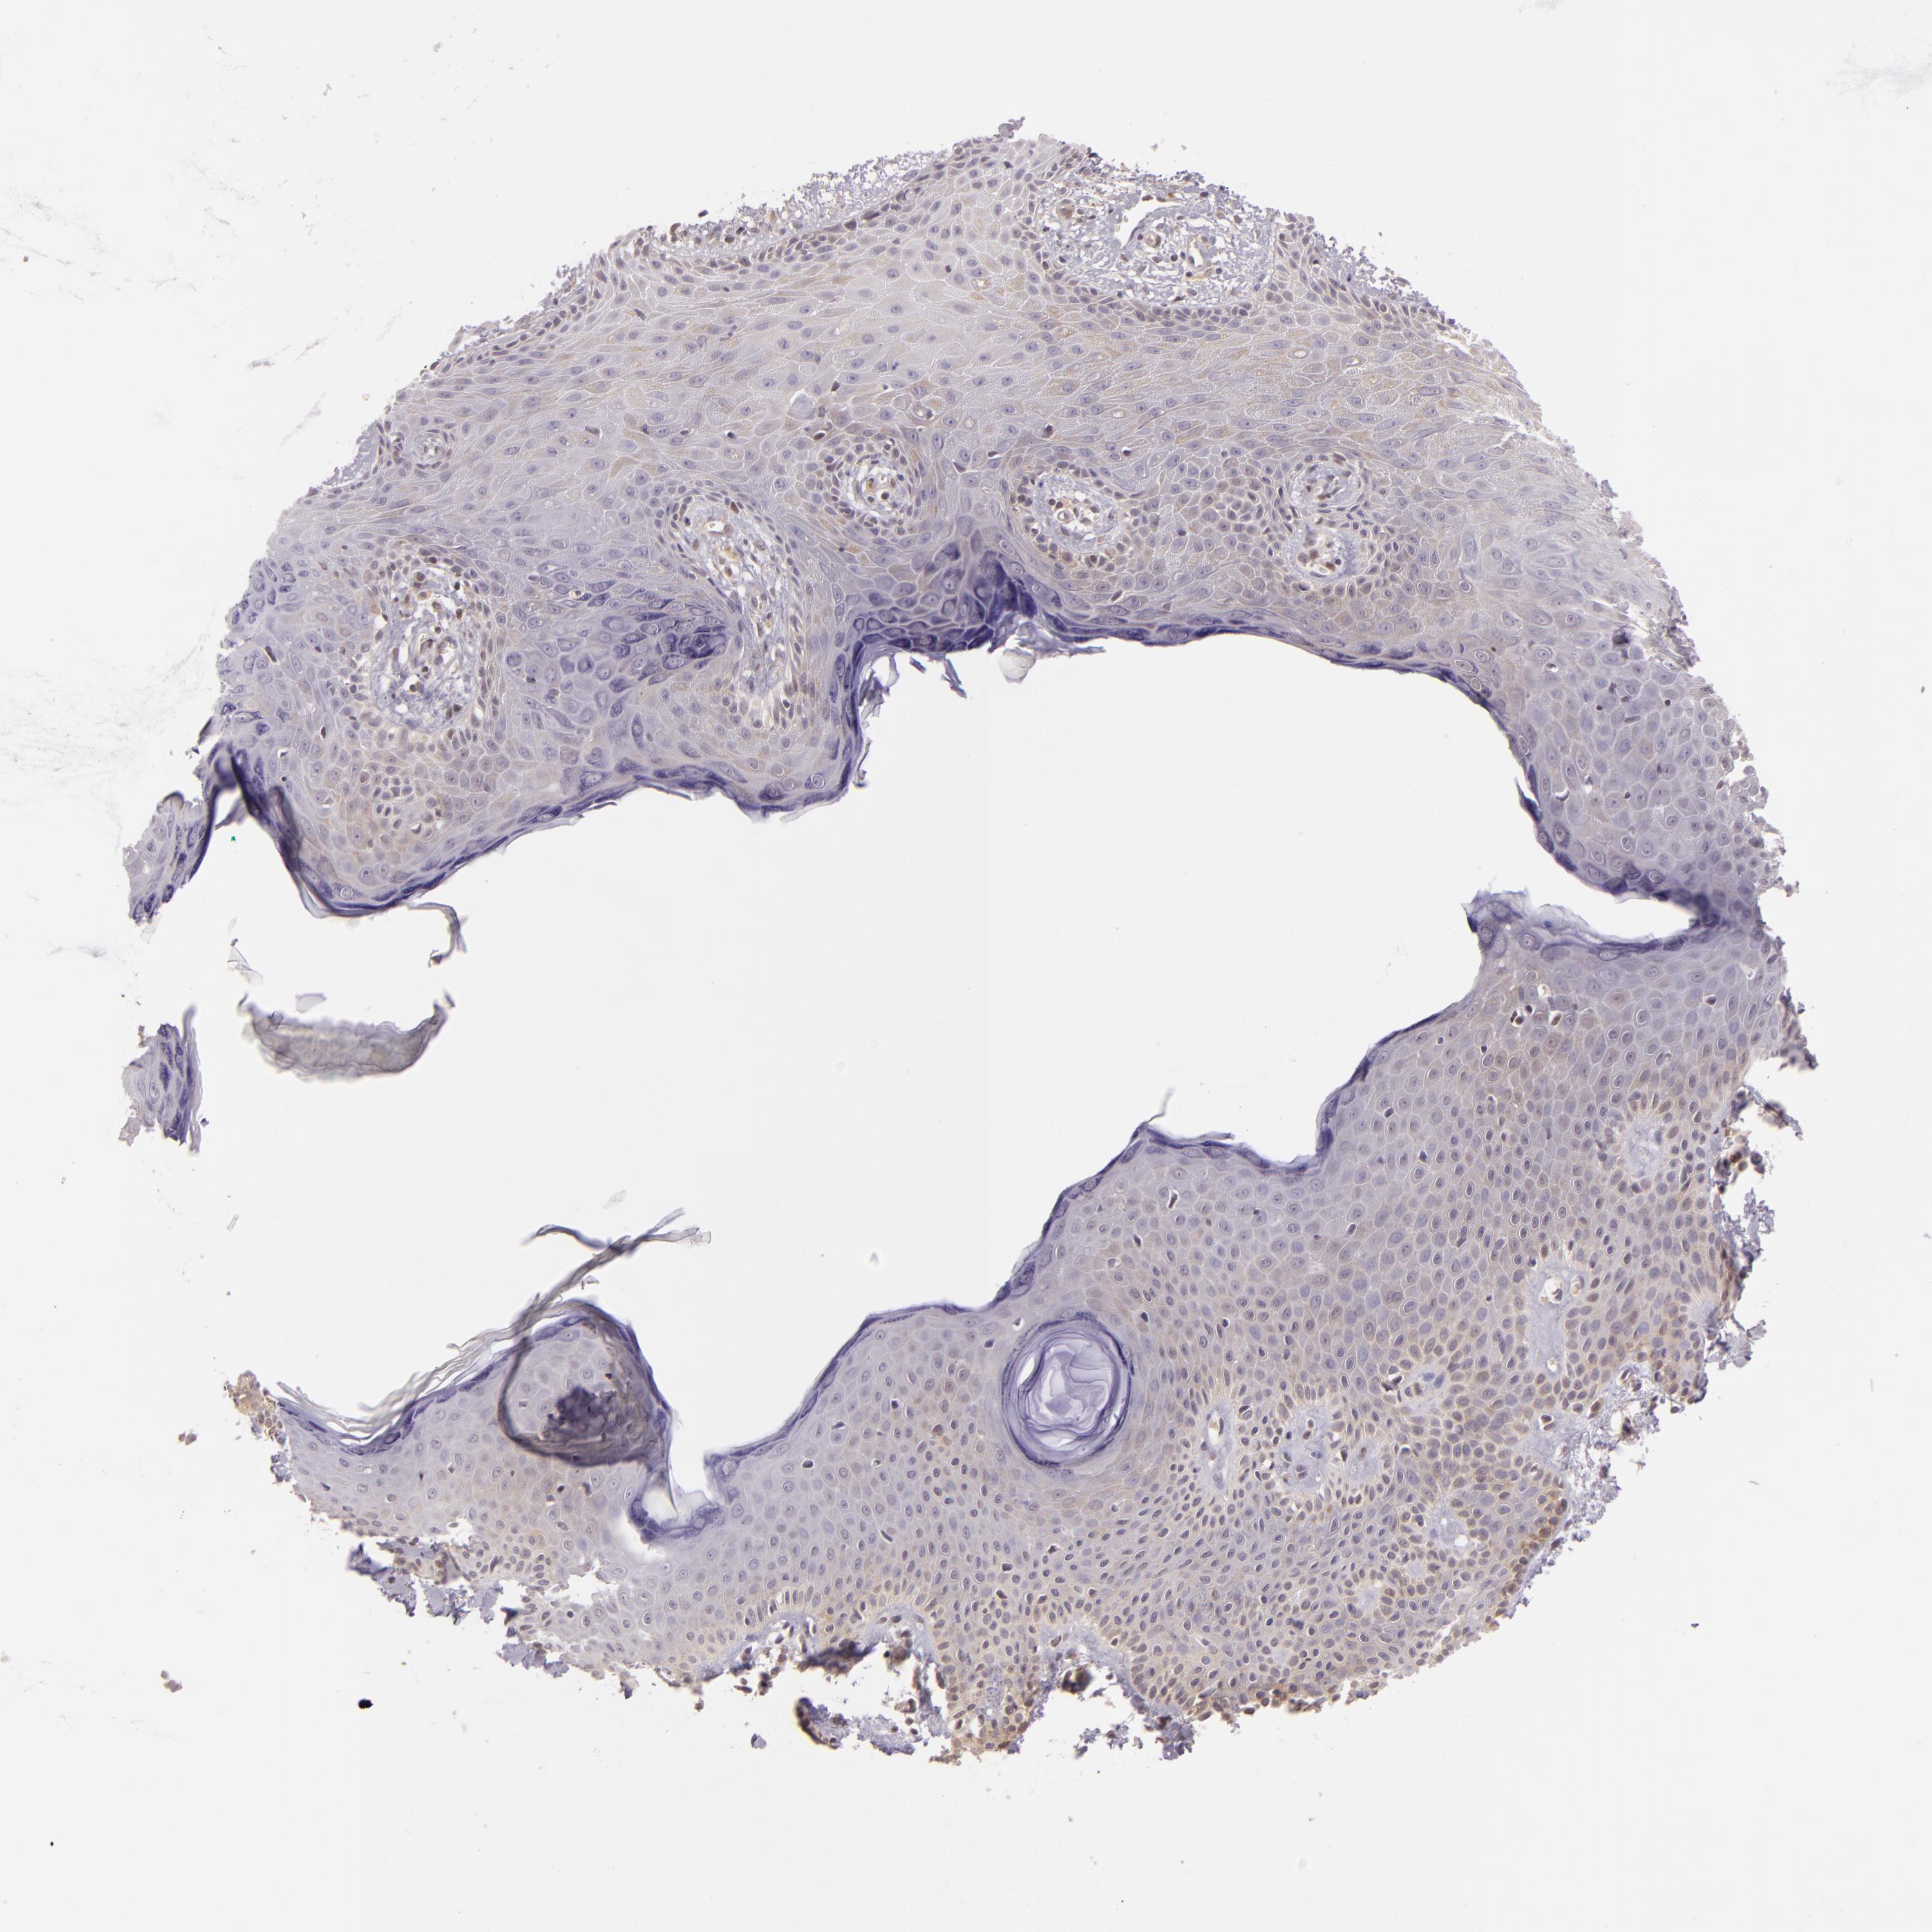

SKIN CANCER - Protein expressioni

A mouse-over function shows sample information and annotation data. Click on an image to view it in a full screen mode. Samples can be filtered based on level of antibody staining by selecting one or several of the following categories: high, medium, low and not detected. The assay and annotation is described here.

Antibody staining in the annotated cell types in the current human tissue is reported as not detected, low, medium, or high, based on conventional immunohistochemistry profiling in selected tissues. This score is based on the combination of the staining intensity and fraction of stained cells.

Each image is clickable and will lead to virtual microscopy that enables deeper exploration of all samples and also displays staining intensity scores, fraction scores and subcellular localization as well as patient and tissue information for each sample.

Antibody HPA001400

Staining

High

Medium

Low

Not detected

Intensity

Strong

Moderate

Weak

Negative

Quantity

>75%

75%-25%

<25%

None

Location

Nuclear

Cytoplasmic/membranous

Cytoplasmic/membranous,nuclear

Squamous cell carcinoma, NOS

Basal cell carcinoma